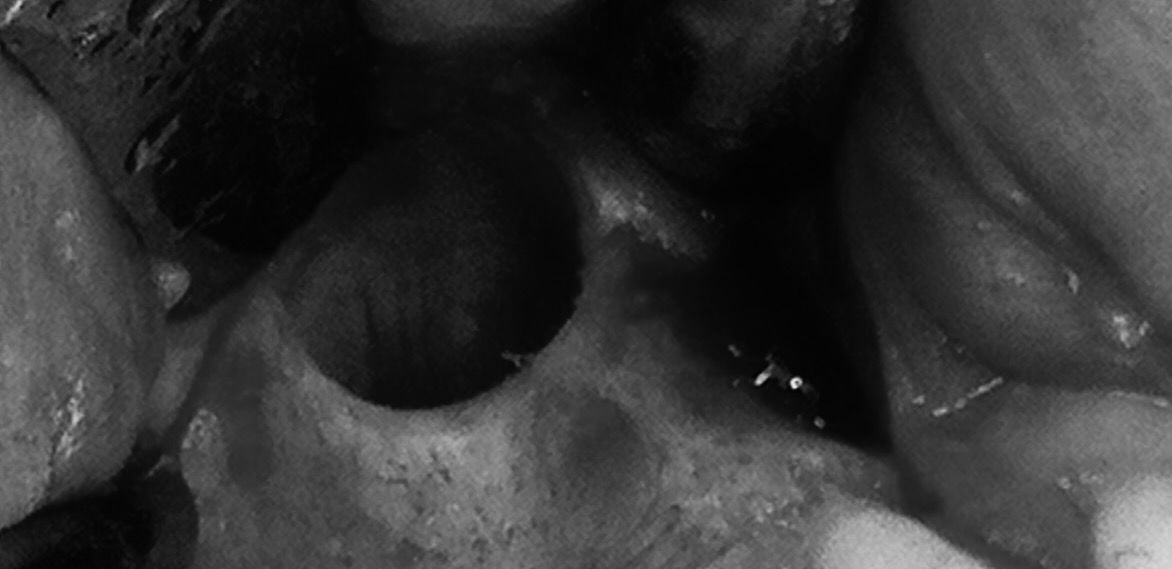

Canino incluso

Posizione orizzontale del canino

Rimozione chirurgica del canino incluso

Risultato finale